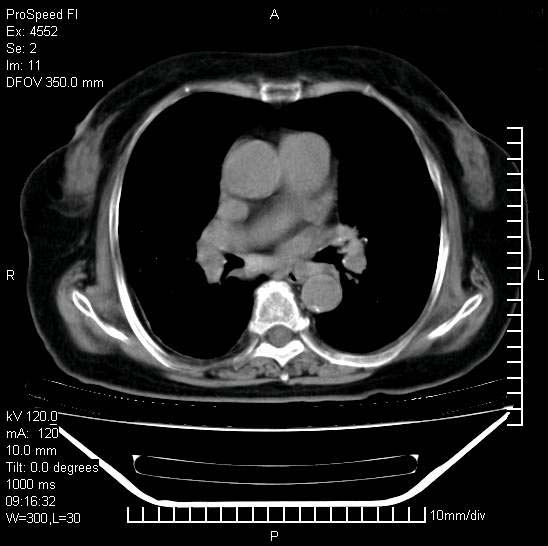

十几年前曾患肺结核,一周前突咳血约100ml,中性粒细胞稍高,诊断两上肺陈旧结核,下肺炎症,给予抗炎治疗,近几日晚上高热,39度,仍咳少量血,4天前ct及今天ct上传。

[face=黑体]8月30日[/face]

今天ct

短短几天内,病变范围明显增多扩大,以左侧明显,而且双侧出现胸水,还是考虑感染.

短短几天内,病变范围明显增多扩大,以左侧明显,而且双侧出现胸水,我更多考虑左侧中心性肺癌并并阻塞性不张及肺炎,炎症变化也太快了!

无论是肿瘤还是炎症4天的时间都发展够快的,并且还在治疗中,如果说是左肺癌那么右肺的病变不好解释,本人更加倾向于炎症,左肺舌叶支气管被痰栓或血凝块堵塞,造成阻塞性肺炎。

1)两肺结核并感染。2)不排除左肺上叶中央型肺癌并阻塞性肺炎、肺不张可能;建议行纤支镜检查。3)右肺门及纵隔淋巴结肿大。4)双侧胸腔积液。